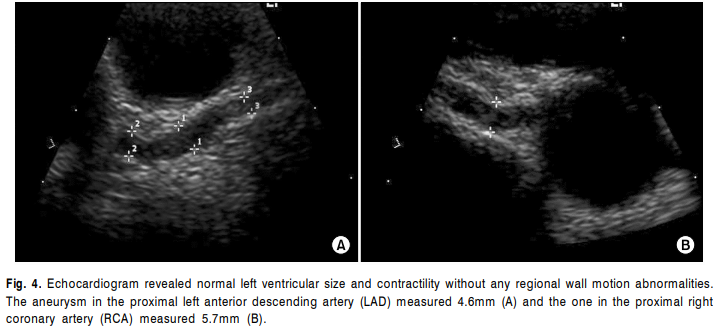

검사소견: 환아는 내원 당시 말초혈액검사에서 혈색소 10.4g/dL, MCV 57.7fL, MCH 17.9pg, MCHC 31.0g/dL, 백혈구 4,650/mm3(호중구 70%, 림프구 22%, 단핵구 6%, 호산구 1%, 호염기구 1%), 혈소판 205,000/mm3이었고, 화학검사상 AST/ALT 84/50IU/L, 총 빌리루빈 0.27mg/dL, LDH 762IU/L, ferritin 57.8ng/mL, 중성지방 190mg/dL이었다. C-반응성 단백질은 0.95mg/ dL이고 EBV IgG, EA IgG, EBNA IgG, EBV PCR은 양성이었다. 조혈모세포이식을 준비하기 위하여 시행한 심장 초음파 검사에서 좌우 관상동맥이 각각 4.6mm, 5.7mm로 늘어난 소견이 관찰되었으며(Fig. 4), 심전도와 흉부 방사선검사에서 특이소견은 없었다.

EBV와 연관되어 10~15%에서 간비대가 오며, 간 효소의 상승은 80% 이상에서 발병 2~3주경에 나타나 발병 5주경에 정상으로 되는데 이 중 약 5~25%에서는 혈청 빌리루빈 수치도 상승한다. 만성활동성 EBV 감염이 간에 영향을 미치는 경우 비특이적 간염에서 간경화까지 다양한 임상 양상으로 나타날 수 있는데, 자가면역 간염과의 연관성에 대해서 Vento 등은 억제/유발 T 세포의 유전적 결함이 있는 환자에서 EBV에 감염된 B 세포가 간세포에 표현되어 있는 asialoglycoprotein 수용체에 항체를 생성하여 간염이 유발된다고 보고한 바 있다. 만성활동성 EBV 감염과 연관된 자가면역 간염의 경우 스테로이드 치료로 수 년간은 일시적인 회복을 보일 수 있으나, 예후가 매우 불량하여 결국에는 몇 년 안에 혈액학적 또는 비혈액학적 원인에 의해 사망할 가능성이 매우 높다. 환아의 경우 EBV IgG, EA IgG, EBNA IgG, EBV PCR이 지속적으로 양성이면서 전염단핵구증의 증상이 악화되는 경우 면역글로불린과 스테로이드를 사용하면 증상이 호전되는 것을 관찰할 수 있었으며 완치를 위해 조혈모 세포이식을 준비하던 중 시행한 심장 초음파에서 우연히 관상동맥류를 발견하게 되었다.

만성활동성 EBV 감염으로 인한 심장이나 폐에 대한 합병증은 1993년 Kikuta 등이 처음 보고하였는데, 관상동맥류를 동반한 만성활동성 EBV 감염 환자에서 심근과 대동맥 조직에서 EBV 유전자를 중합효소연쇄반 응법으로 증명하였다. 이후 부검상에서 거대 관상동맥 류와 대동맥류가 보고되고 양측성 관상동맥류도 발견 됨으로써 관상동맥류는 만성활동성 EBV 감염의 증상들 중 하나로 생각되고 있다. 또한 만성활동성 EBV 감염으로 인해 사망하는 환자의 경우 그 사인이 심부전, 신부전, 림프증식성질환의 순으로 나타나고 있으며, 심혈관계 합병증은 15세 이전에 발생하는 경우가 대부분으로 이에 대한 주의가 필요하다. 만성활동성 EBV 감염과 연관된 관상동맥류의 병인은 아직 정확히 밝혀진 바는 없으나 EBV에 감염된 림프구에 의한 작용으로 추정한다.